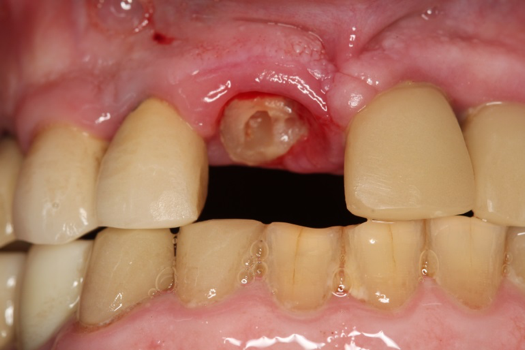

After 4 months of healing and integration of the bone around the implant, the digital workflow was initiated to develop the abutment and treatment plan. Another analog impression was made with an impression post and polyvinyl impression. The laboratory scanned the impression and digitized it to create the emergence profile of the milled titanium abutment and the final restoration (Figure 10 and Figure 11). The patient had a considerably thick soft-tissue profile, allowing a milled titanium abutment. The decision to use a titanium abutment was based on the patient's occlusion and propensity to fracture teeth or restorations. The virtual model was gray because the scanner does not recognize the color of the analog impression. The virtual final abutment and crown were approved and fabrication completed. The final restoration met the patient's esthetic values and his ability to function (Figure 12 and Figure 13).

Fig 10. Titanium abutment proposal.

Figure 10

Fig 11. Final crown proposal.

Figure 11